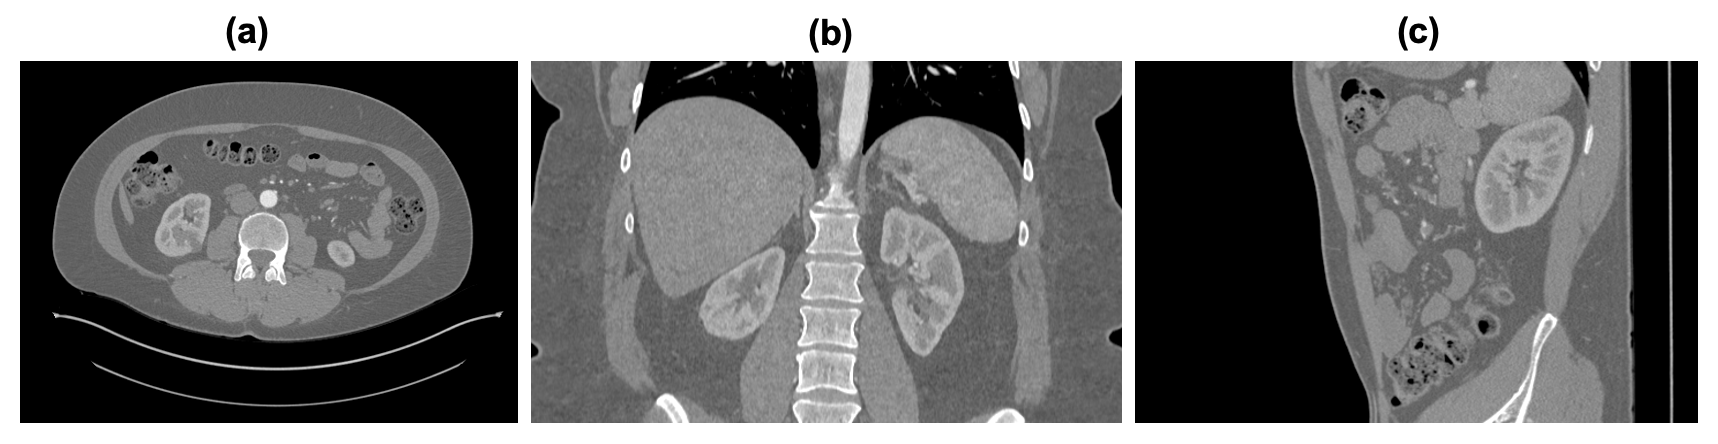

3.4.1 Image Planes: Axial, Coronal, and Sagittal

CT images can be acquired in multiple planes as shown in Fig. 3, including axial, coronal, and sagittal views, which provide different perspectives of the body:

• Axial (Transverse) Plane: This is the most common orientation, providing cross-sectional images of the body in horizontal slices [14]. Each slice corresponds to a specific thickness, typically ranging from 1 to 10 mm, allowing for detailed examination of organs and structures.

• Coronal Plane: This orientation provides images viewed from the front, slicing the body into anterior and posterior sections [14]. Coronal views are particularly useful for visualizing structures such as the sinuses, heart, and lungs.

• Sagittal Plane: These images divide the body into left and right sections, offering insights into the midline structures [14]. Sagittal views help assess spinal alignment and certain anatomical relationships.

Refer to caption

Figure 3: Kidney CT scan taken from [14] - Fig. 3(a) axial, 3(b) coronal, and 3(c) sagittal plane